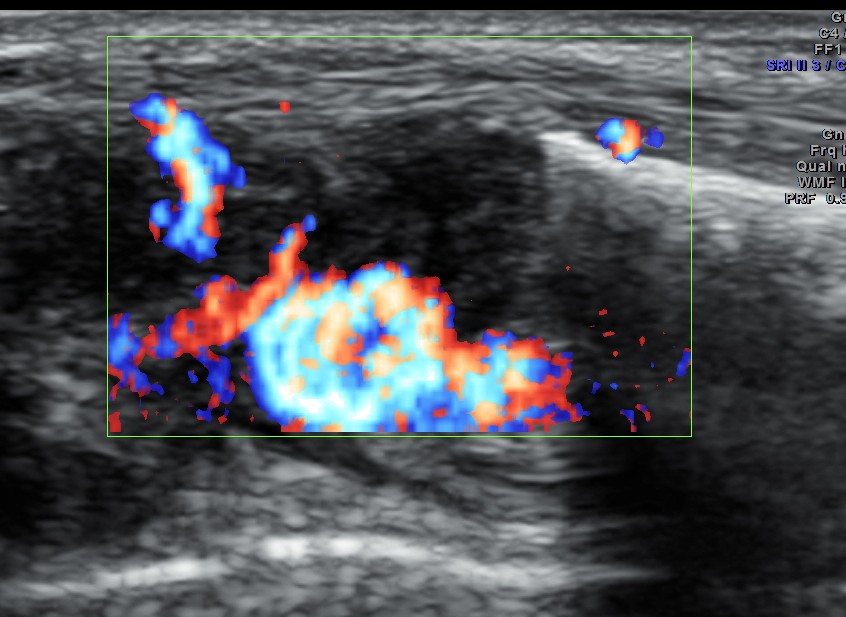

Colour Doppler showed increased vascularity all around .

A diagnosis of an abscess in formation was offered and the child recovered well with appropriate treatment.

This case is presented to illustrate how musculo skeletal ultrasound and colour Doppler can be very useful to assess soft tissue pathology.